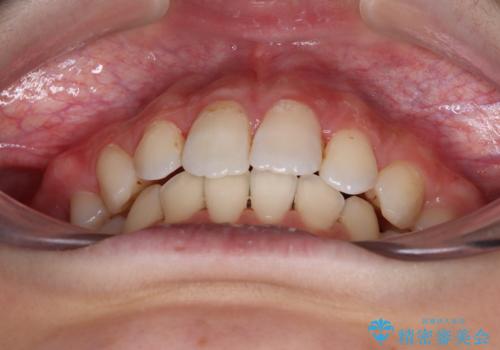

- 上顎前歯の突出感を気にして来院された患者様です。

舌の突出癖などにより、上下前歯の間に指が入るくらい隙間のできる状態でした。

下顎は叢生があったため、上下左右の第一小臼歯4本を抜歯し、更には口元の突出感を大きく改善させるために、上顎臼歯を後方に移動させるための補助装置をしようし、ワイヤー装置にて矯正治療を行うこととしました。